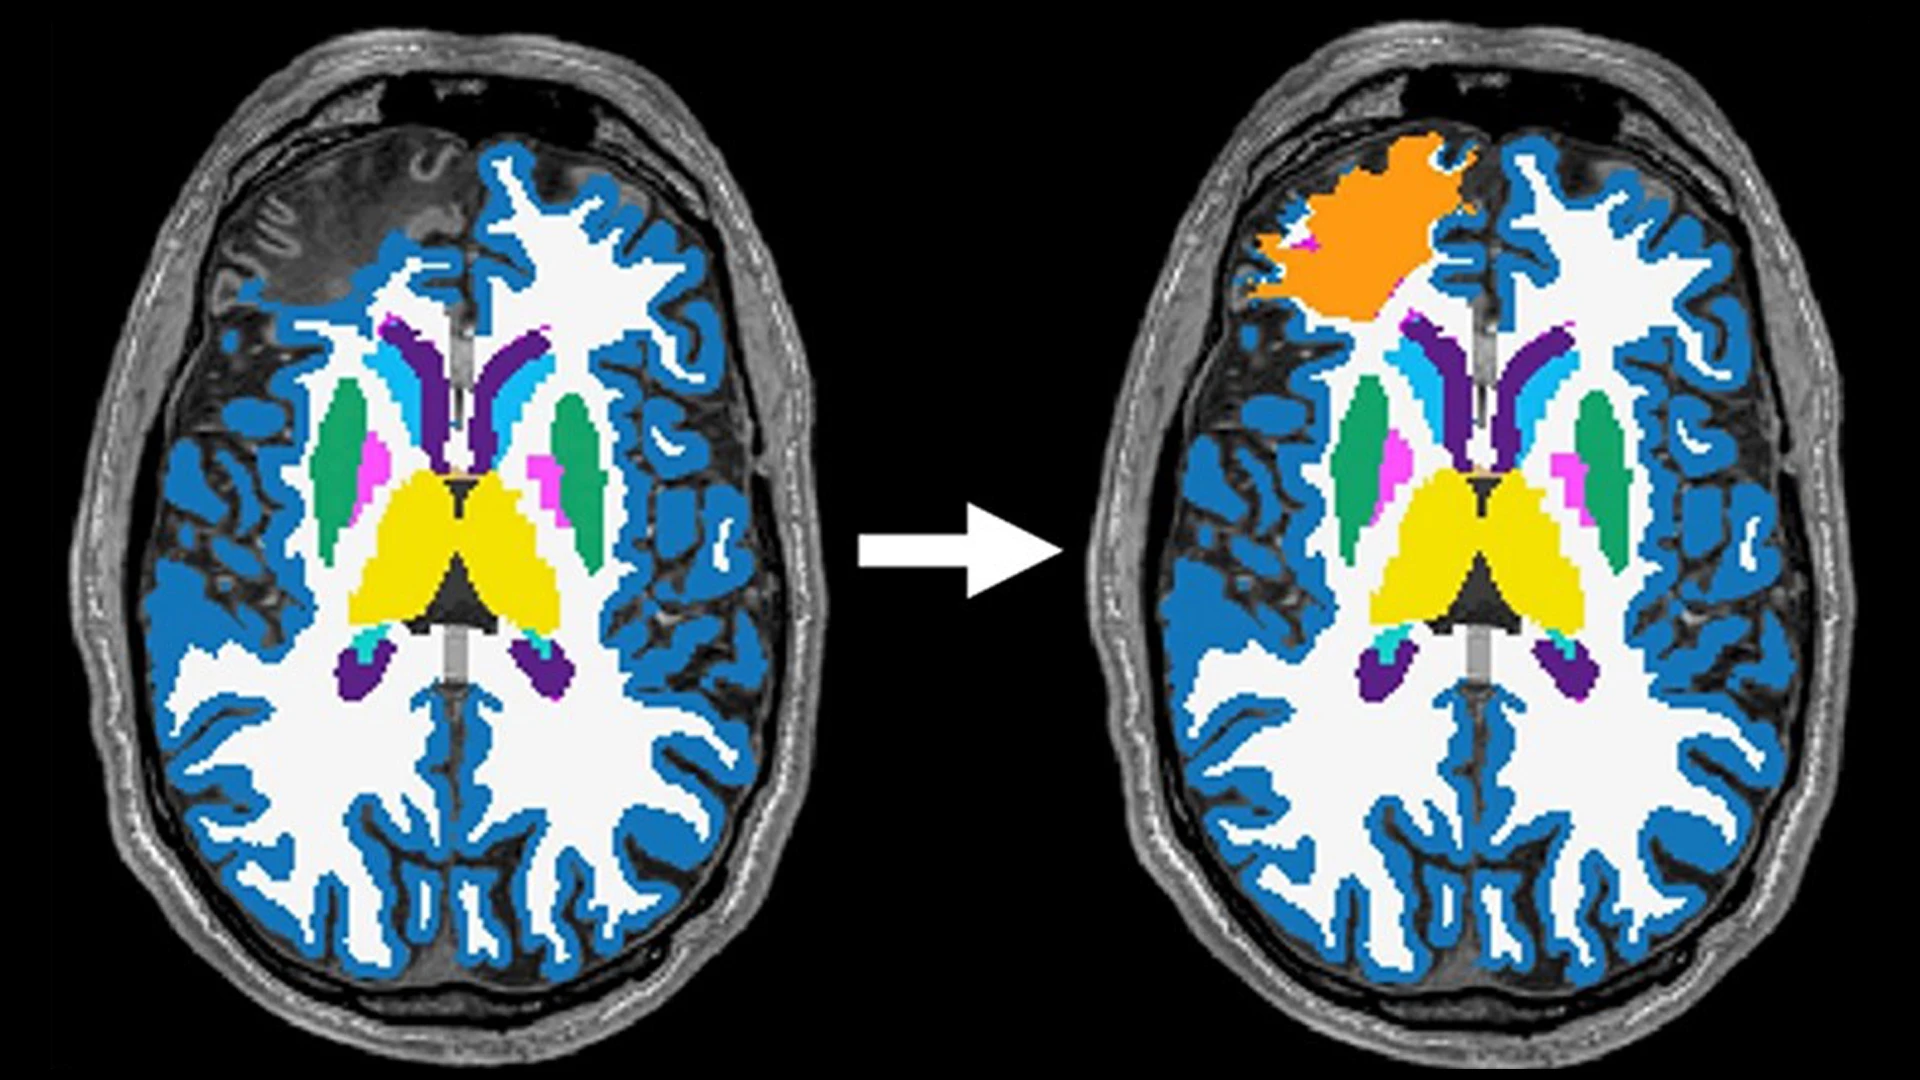

This necessitated developing an innovative lesion correction methodology to enable brain volume estimations among patients with large cortical lesions who would otherwise be excluded—a huge innovation in the field of TBI research, according to Dr. Kumar.

“Large brain lesions are quite common after significant TBI, and most off-the-shelf imaging software cannot handle these lesions to accurately calculate brain volumes from MRIs,” says Dr. Kumar. “Our LETBI investigator team, led by our collaborator Dr. Brian Edlow and his lab at Harvard, developed a way to accurately calculate volumes for these participants with lesions so we could include them in this analysis, which lessens the likelihood of a biased sample.”

Cortical lesions can be a common feature of traumatic brain injury. However, as cortical lesions can lead to inaccurate surface renderings in automated segmentation pipelines, patients with large lesions could be excluded from studies, which can contribute to non-random missingness bias and limits the generalizability of findings. In this phenotype study, the team applied a lesion-correction methodology, which screened all T1-weighted images for the presence of cortical lesions. Lesions that disrupted the cerebral cortex were traced by a study investigator, and multiple investigators confirmed that cortical lesion tracings covered the entire lesioned area and that the lesion boundary did not extend into ventricles. Investigators then merged cortical lesions with the initial white matter segmentation, generating a "lesion-corrected" white matter mask.